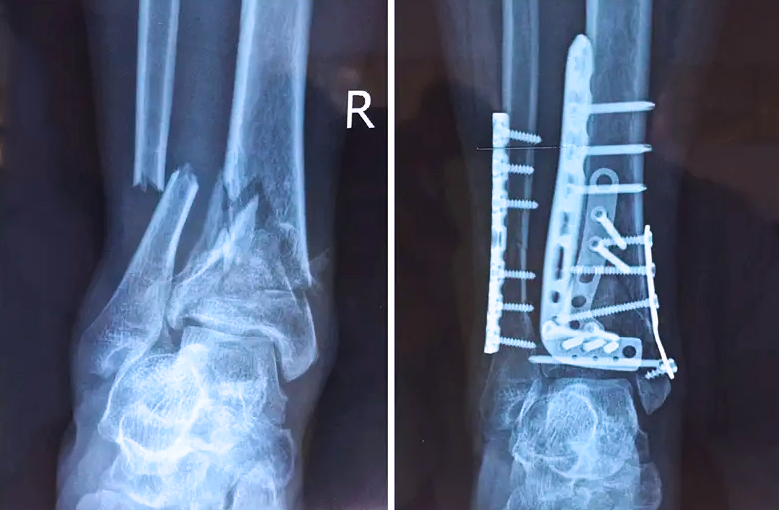

對(duì)于骨科醫(yī)生而言,關(guān)節(jié)外的骨折是相對(duì)比較簡(jiǎn)單的,因?yàn)殛P(guān)節(jié)外的骨折允許我們復(fù)位的時(shí)候有一些偏差,但是如果骨折部位在關(guān)節(jié)內(nèi),我們就不能有任何的偏差。而且關(guān)節(jié)內(nèi)的骨折是有關(guān)節(jié)面的,如果關(guān)節(jié)面不平整,就會(huì)導(dǎo)致患者以后出現(xiàn)創(chuàng)傷性關(guān)節(jié)炎等癥狀,或者出現(xiàn)長(zhǎng)時(shí)間的疼痛,甚至造成殘疾。所以對(duì)于關(guān)節(jié)內(nèi)的骨折,一定要做到“解剖復(fù)位”,就像搭積木一樣,每個(gè)積木塊、每個(gè)碎骨塊都要完好的拼到一起,做到嚴(yán)絲合縫。

踝關(guān)節(jié)是人體中負(fù)重較大的關(guān)節(jié),也是活動(dòng)度較大的地方,所以對(duì)于足踝部位的關(guān)節(jié)內(nèi)骨折,我們更需要做到“解剖復(fù)位”。對(duì)于這種關(guān)節(jié)內(nèi)的骨折,尤其是踝關(guān)節(jié)內(nèi)部的骨折,不僅需要進(jìn)行X影像平片正側(cè)位的拍攝,由于在二維影像上無法判斷關(guān)節(jié)面的受損情況,往往還需要進(jìn)行三維影像的檢查。

在術(shù)前,我們需要做三維掃描的CT檢查,我們必須要有CT的片子,還要有三維的重建。

在術(shù)中,我們?cè)趺慈ヅ袛嚓P(guān)節(jié)面平不平整呢?常規(guī)的正側(cè)位影像是不能判斷的。有些醫(yī)生為了準(zhǔn)確的判斷,可能會(huì)選擇做開放性的手術(shù),把關(guān)節(jié)暴露出來,在眼睛的直視下判斷關(guān)節(jié)面平不平整。但是關(guān)節(jié)全部打開,無疑增加了病人的創(chuàng)傷,而且增加了患者的恢復(fù)時(shí)間。所以如果在術(shù)中我們有三維影像的支持,對(duì)醫(yī)生做手術(shù)而言就會(huì)事半功倍,而且能夠大大的增加手術(shù)準(zhǔn)確度,增加患者術(shù)后的預(yù)后。所以在術(shù)中有三維影像的支持是非常必要的!